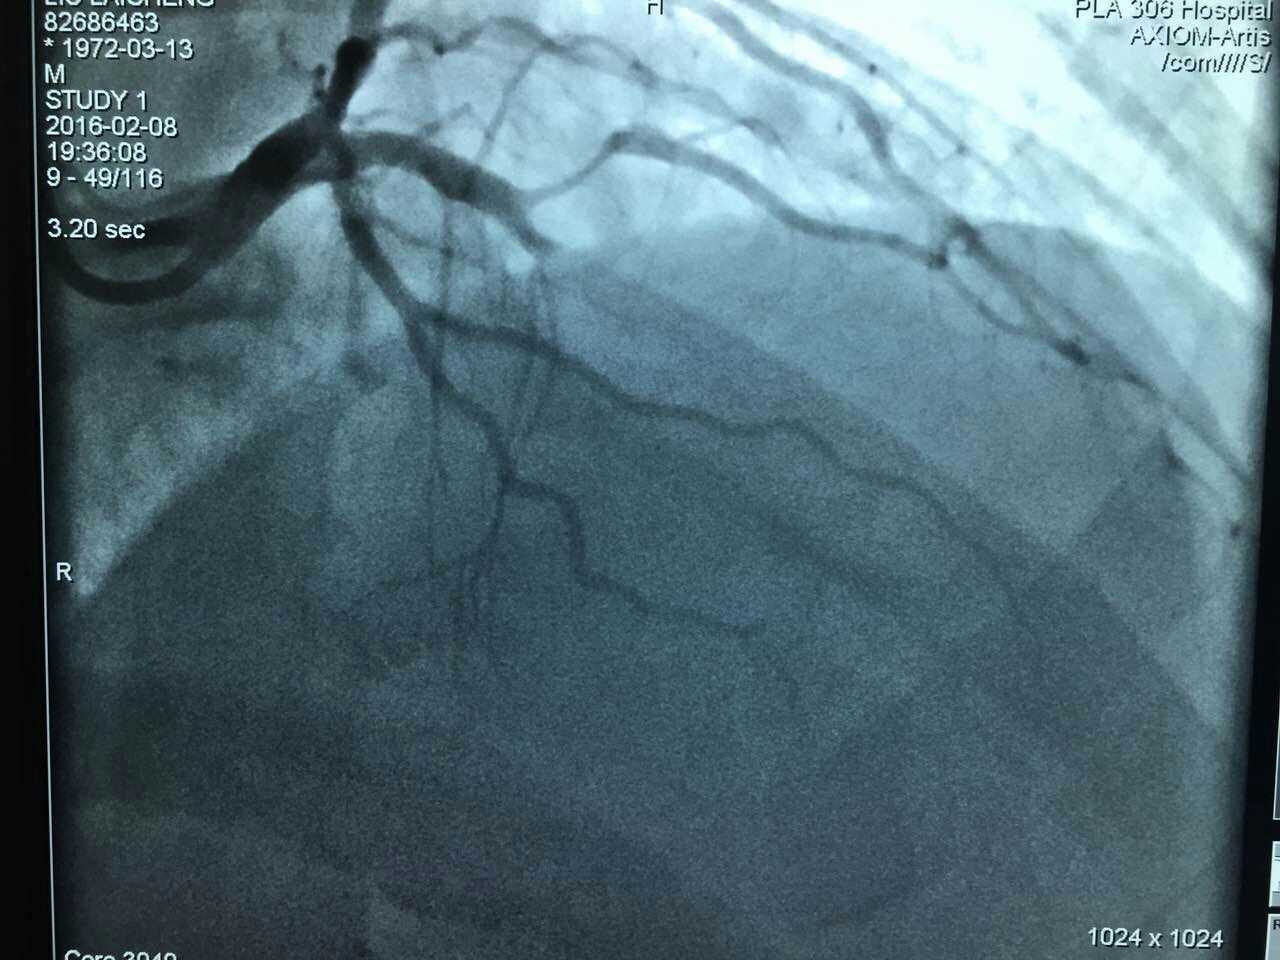

心脏内科专家王守力教授呼吁:谨防节日病,尤其是中青年。大年初一继凌晨抢救一例心梗患者,该团队又为一例中年患者AMI(急性心梗)进行了疏通手术,手术团队24小时待命状态。小编为他们点赞。